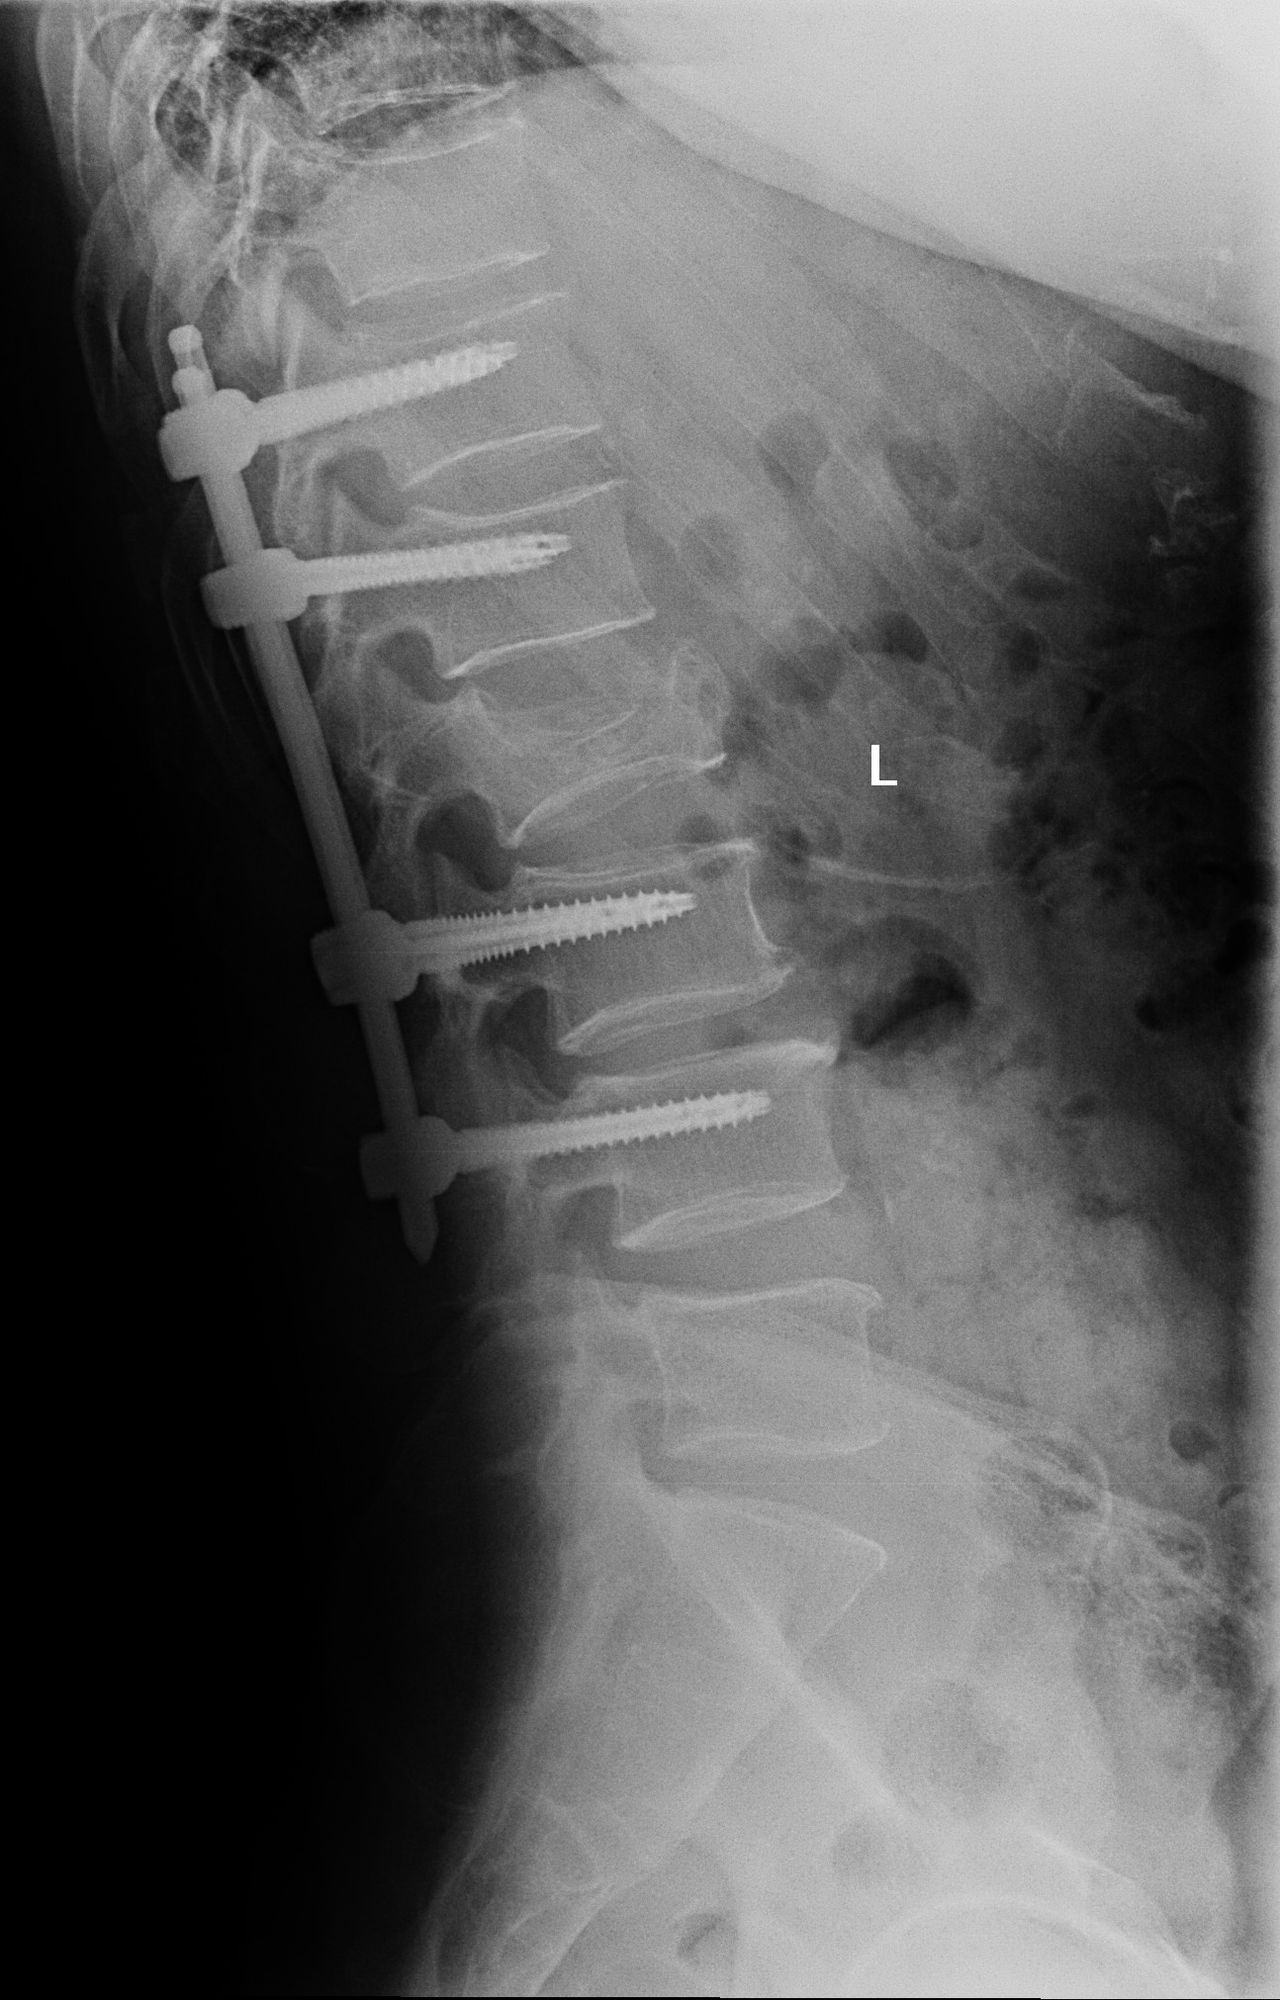

Zdjęcia i filmy